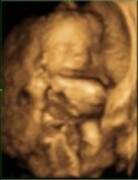

Tak jsem dnes byla na ultrazvuku v 8tt a miminko už bylo krásně vidět a tlouklo mu i Řeknu Je to tak krásný pocit to vidět. Uronila jsem přitom i pár slz. Teda chtělo se mi spíš hodně brečet štěstím Podle UT je stáří miminka 7+2tt, takže je o něco mladší a menší. Mám konečně i fotečku, ale není moc povedená. Brala to z nějakého divného úhlu, takže tam není moc vidět, ale na obrazovce jsem viděla podobu miminkaTak jsem konečně tu :-)